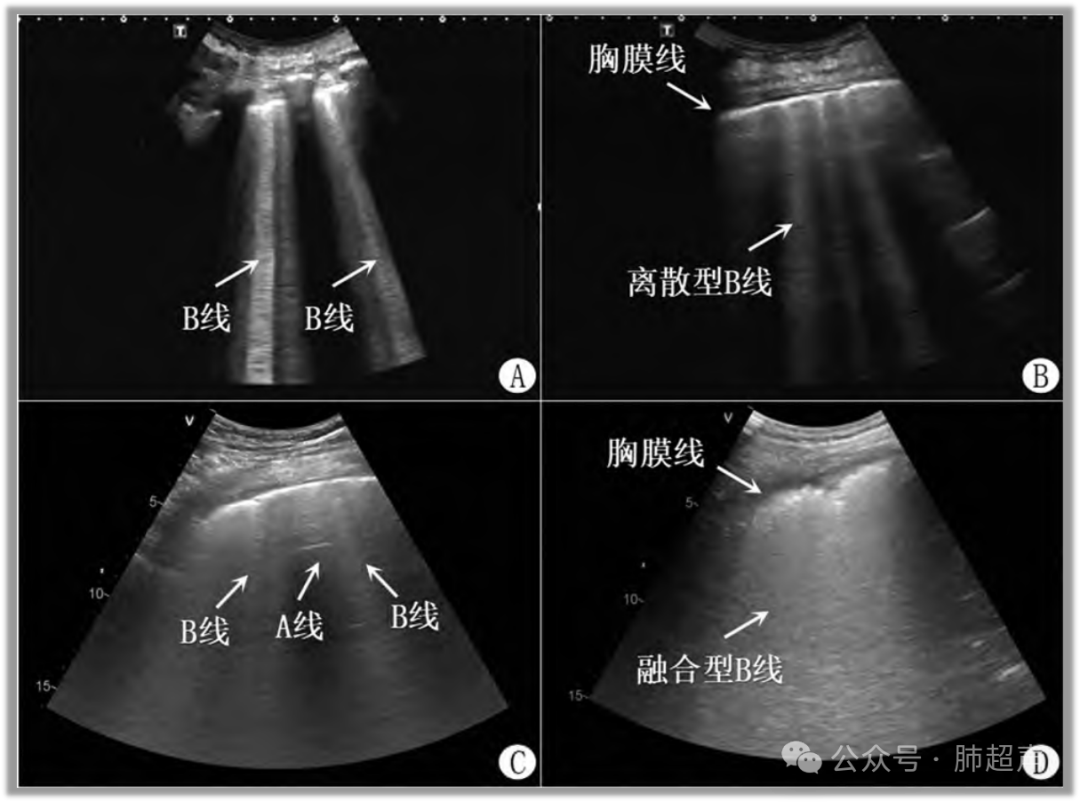

(1) B线:心源性肺水肿多为连续性、弥漫性B线,胸膜线清晰光滑,随呼吸可见滑动;肺源性肺水肿以急性呼吸窘迫综合征(acute respiratory distress syndrome,ARDS)常见,B线分布无规律性,呈多发局灶性或弥漫性渗出,胸膜线随病变轻重表现为轻微或明显不均匀(图3)

(2) 肺实变:心源性肺水肿出现肺实变多为胸腔漏出液压缩肺叶所致,肺叶受压,容积减小,回声尚均匀; ARDS肺实变为肺泡渗出增多导致,回声杂乱不均,可见多发碎片征及支气管征,伴少量或无胸腔积液。

图3  不同肺水肿超声表现

注:A、B. 心源性肺水肿,胸膜光滑均匀,纵切面显示多肋间连续分布B线,横切面显示弥漫分布B线;C. 轻度急性呼吸窘迫综合征(ARDS),多条B线之间可见 “保留区域”,提示不均匀渗出;D .重度ARDS,大片融合B线并胸膜线不均匀。